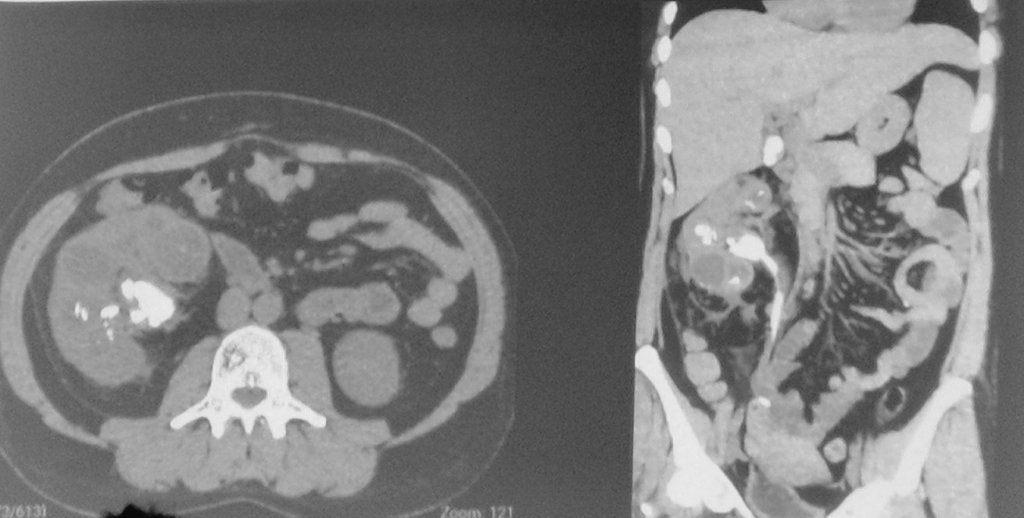

39 years old, septic, previous double j and nefphrostomy for draining. No success. 3nd post-op of laparoscopyc nephrectomy, discharged home today.

#UroSoMe#UroSoMeBrasil pic.twitter.com/yGnovMXEDv – mjesto: Hospital de Clínicas da UFPR